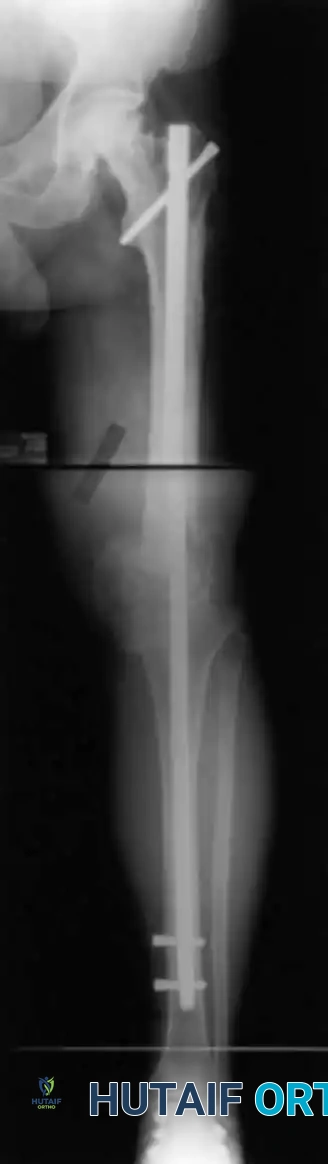

2. Arthrodesis with Intramedullary Nailing

Intramedullary (IM) nailing is the gold standard when extensive bone loss precludes the use of compression across broad cancellous surfaces (e.g., post-tumor resection, failed hinged TKA).

Advantages: Immediate structural stability, early full weight-bearing, absence of pin-track complications, higher fusion rates (85% to 100%), and superior patient comfort.

Disadvantages: Significant intraoperative blood loss, technically demanding alignment control, and the risk of disseminating localized infection throughout the entire medullary canal.

Surgical Technique:

* Infection Management: In cases of infected TKA, a strict two-stage procedure is mandatory. Stage one involves complete hardware explantation, radical debridement, and placement of an articulating or static antibiotic-impregnated cement spacer, followed by a 6-week course of targeted intravenous antibiotics.

* Nail Insertion: Once infection is eradicated, the bony surfaces are prepared. The medullary canals of the femur and tibia are sequentially reamed using flexible reamers.

* Implant Selection: Long, custom, or modular titanium nails are utilized. The nail must extend at least 4 to 6 cm beyond the isthmus of both the femur and the tibia to ensure adequate diaphyseal purchase.

* Fixation: The femoral segment is often inserted retrograde, and the tibial segment antegrade. The segments are joined via a conical coupling mechanism and stabilized with proximal and distal interlocking screws to control rotation.

* Bone Grafting: The fusion site is meticulously packed with autogenous bone graft (iliac crest or local bone) and allogenic cancellous chips to stimulate osteogenesis.